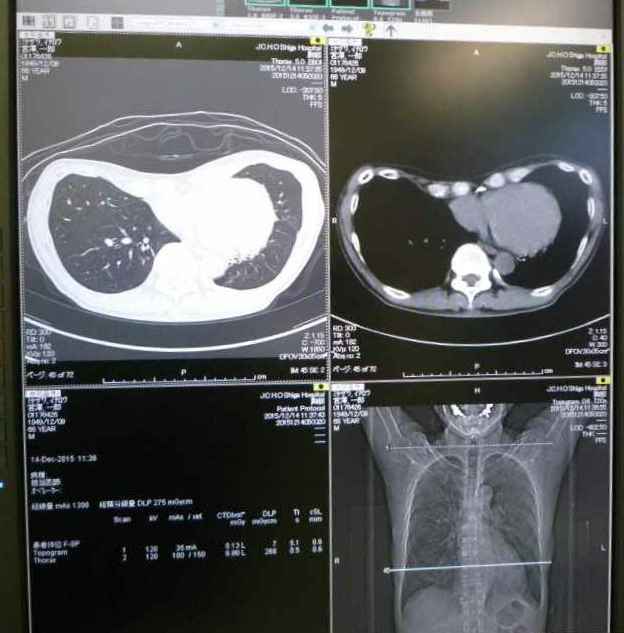

ついでに人間ドックで肺の精密検査が必要といわれていたので検査。

結果は、異常なし。